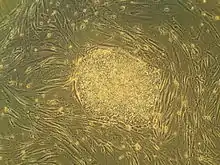

Fosterstamceller, eller embryonale stamceller, er helt "nye" stamceller fra et foster. Stamcellerne kan udvikle sig til at fungere som en hvilken som helst celle i kroppen. Den celleklump, som det befrugtede æg udvikler sig til, består de første 14 dage blandt andet af stamceller, desuden celler der bliver til fosterhinderne og moderkagen; stamceller findes også i blandt andet navlestrengen.